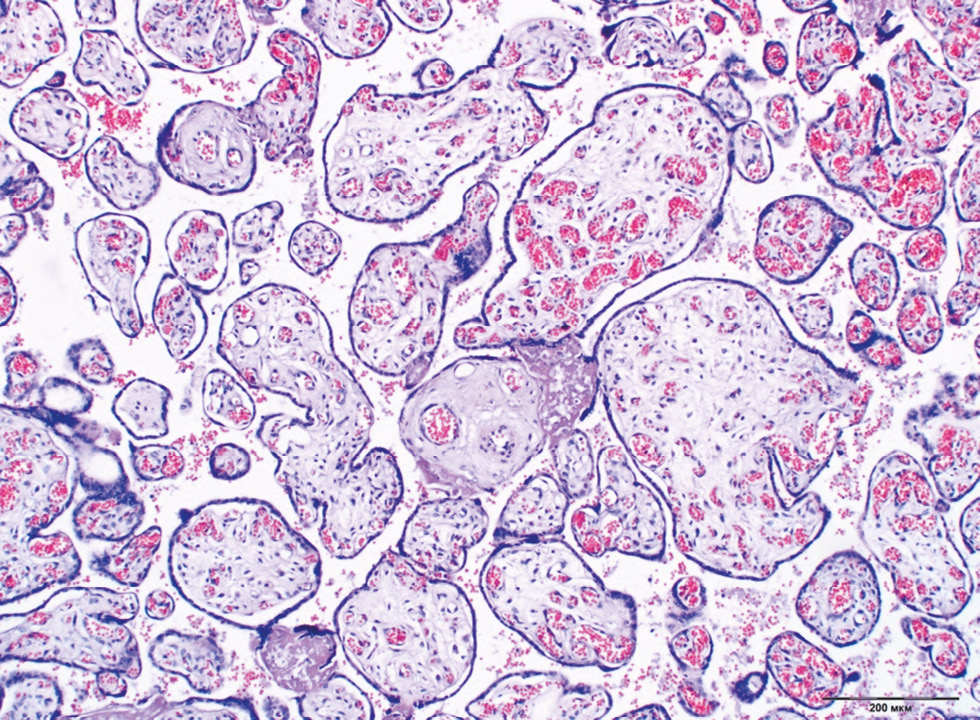

Chronic placental insufficiency was typical for all groups of DM and PE, in contrast to the control group (p < 0.0001). Placental insufficiency was registered in 39.6% of cases in Group 4 (type 2 DM on a diet), 37.2% in the type 1 DM group with MII, whereas pathological immaturity of villi was noted more often in the same groups (14.2% and 19.5%, respectively). In general, pathological immaturity of villi was typical for all groups of DM (9.5%–19.5%, p < 0.0001). The predominance of intermediate immature villi was a characteristic of type 1 DM with MII (13.3%, p = 0.036) (Fig. 1). The dissociated form of chronic placental insufficiency was most often detected in DM (16.3%–26.1%) (Fig. 2). The prevalence of sclerosed villi (0.4%–3.3%) and premature maturation of villi (0.4%–5.0%) were revealed less frequently. In the PE group, the premature maturation of villi was noted often (7.7%, p < 0.0001). In the control group, 93% of placentas corresponded to gestational age (Table 2).

Fig. 2. Dissociated chronic placental insufficiency in type 2 DM. Staining with hematoxylin and eosin, ×100